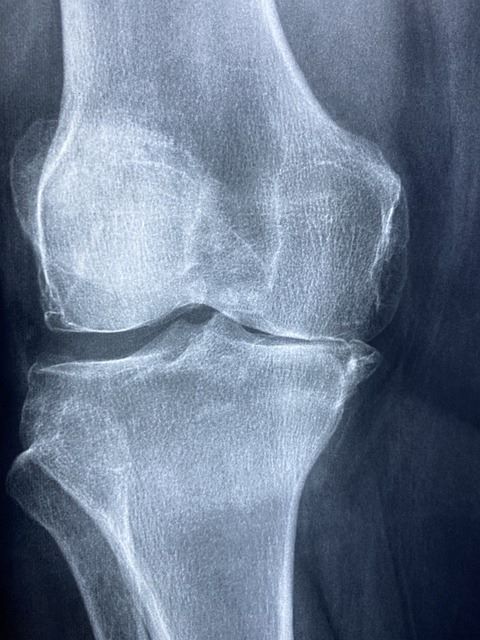

무릎 연골 손상 증상 및 원인 치료 방법

무릎 연골 손상의 대표적인 증상과 연골 손상이 발생하는 원인, 상태에 따른 치료 방법을 알아본다. 그리고 연골 손상 예방법과 사후 관리 노하우까지 살펴본다.

무릎 연골 손상의 대표적인 증상

무릎 연골이 손상되었을 때 가장 먼저 나타나는 증상은 통증이다. 특히 계단을 오르내리거나 무릎을 굽히고 펼 때 통증이 심해지는 경우가 많다. 이어서 관절 부위에 부기나 열감이 나타날 수 있으며, 무릎이 '딱' 하고 걸리는 느낌이 들거나 움직일 때 삐걱거리는 소리가 발생하기도 한다.

심할 경우에는 관절의 움직임이 제한되어 무릎을 완전히 펴거나 구부리기 어려워지고, 무릎 주변 근육이 약화되며 걷거나 앉았다 일어나는 동작이 불편해질 수 있다. 이러한 증상이 지속된다면 연골 손상을 의심해야 한다.